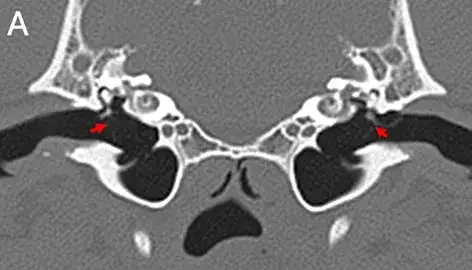

Researchers from the Royal (Dick) School of Veterinary Studies, the Roslin Institute and the University of Edinburgh’s School of Informatics developed their model using CT scan images of dogs’ middle ears – a part of the ear that is frequently affected by disease.

The model was trained to recognise disease using about 500 images, some that showed signs of disease and others that did not, which had been manually interpreted by veterinary experts. This number is fewer than the several thousands that would typically be needed for many AI studies, which would be resource-intensive to generate.

The AI tool was able to make correct diagnoses in 85 per cent of cases. Experts say the result is robust for a relatively small sample size, demonstrating the validity of the approach, and could be improved if additional images were annotated.